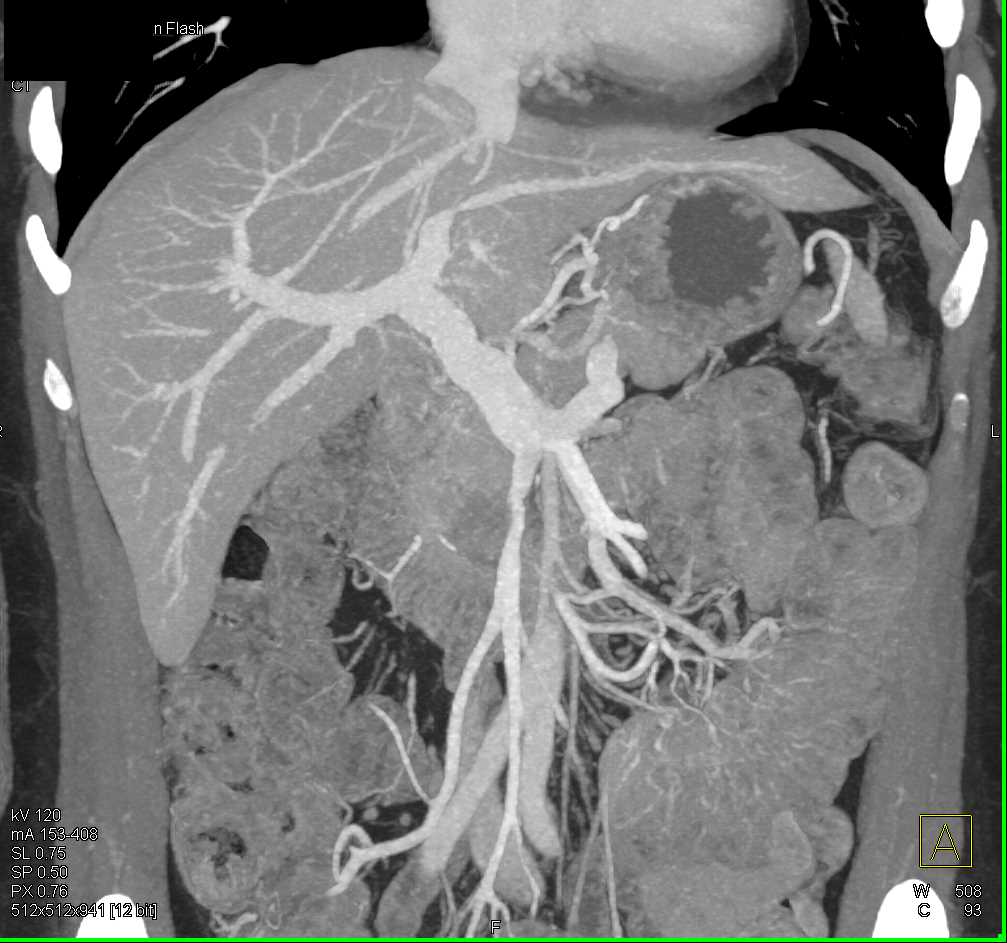

Adenocarcinoma of the Head of the Pancreas